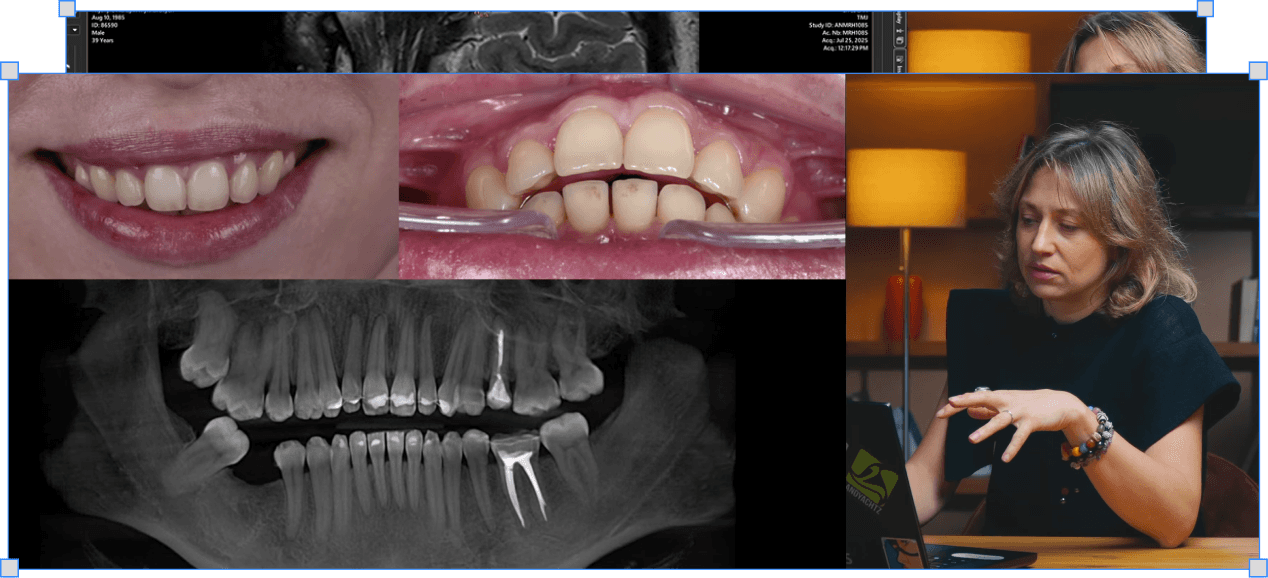

Клінічні кейси: